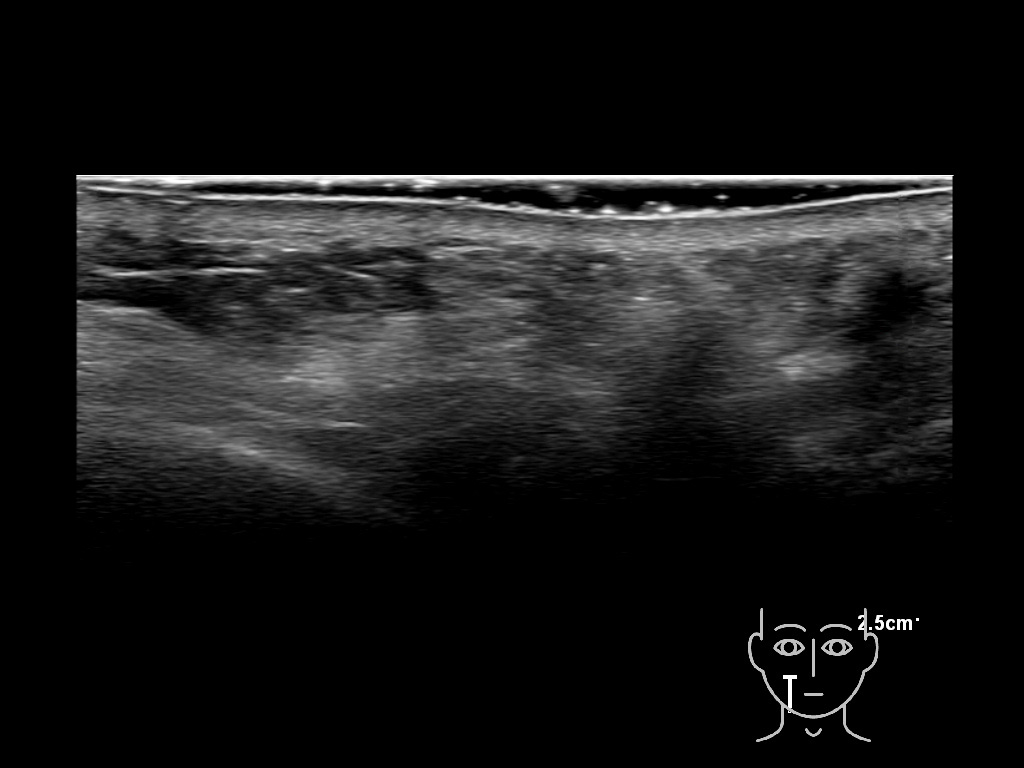

Draw in the second image below where the fillers are located. To check if your answer is correct, swipe the first image to the right.